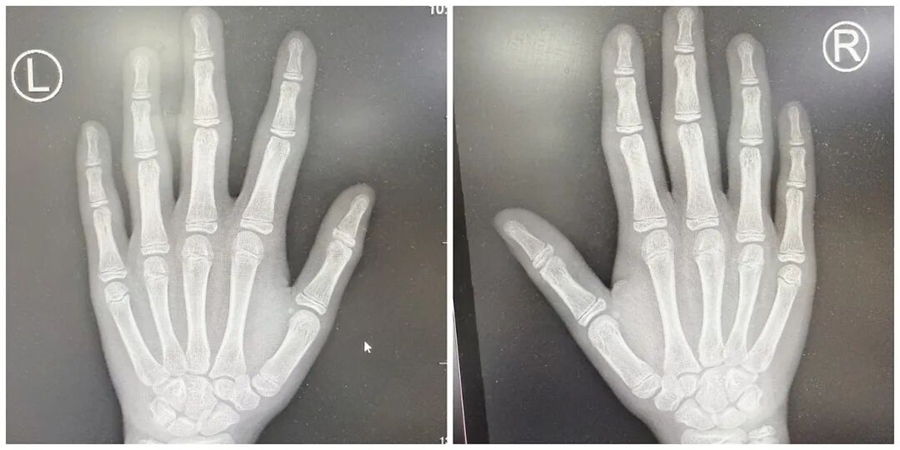

X光片顯示,小燁雙手指間關(guān)節(jié)僅有周圍軟組織腫脹,沒有關(guān)節(jié)間隙狹窄、骨侵蝕、骨膜反應(yīng)或骨質(zhì)疏松等異常,這與類風(fēng)濕關(guān)節(jié)炎等炎癥性關(guān)節(jié)炎的典型表現(xiàn)有著本質(zhì)區(qū)別;

驗(yàn)血結(jié)果也同樣印證了這一點(diǎn),抗 O、類風(fēng)濕因子、ANA、CCP 等炎癥指標(biāo)均為陰性,血沉和 CRP 也處于正常水平。

無系統(tǒng)性炎癥指標(biāo)升高、無自身抗體、無影像學(xué)骨關(guān)節(jié)破壞,且癥狀局限于手指。綜上,小燁最終被明確診斷為厚皮指癥。